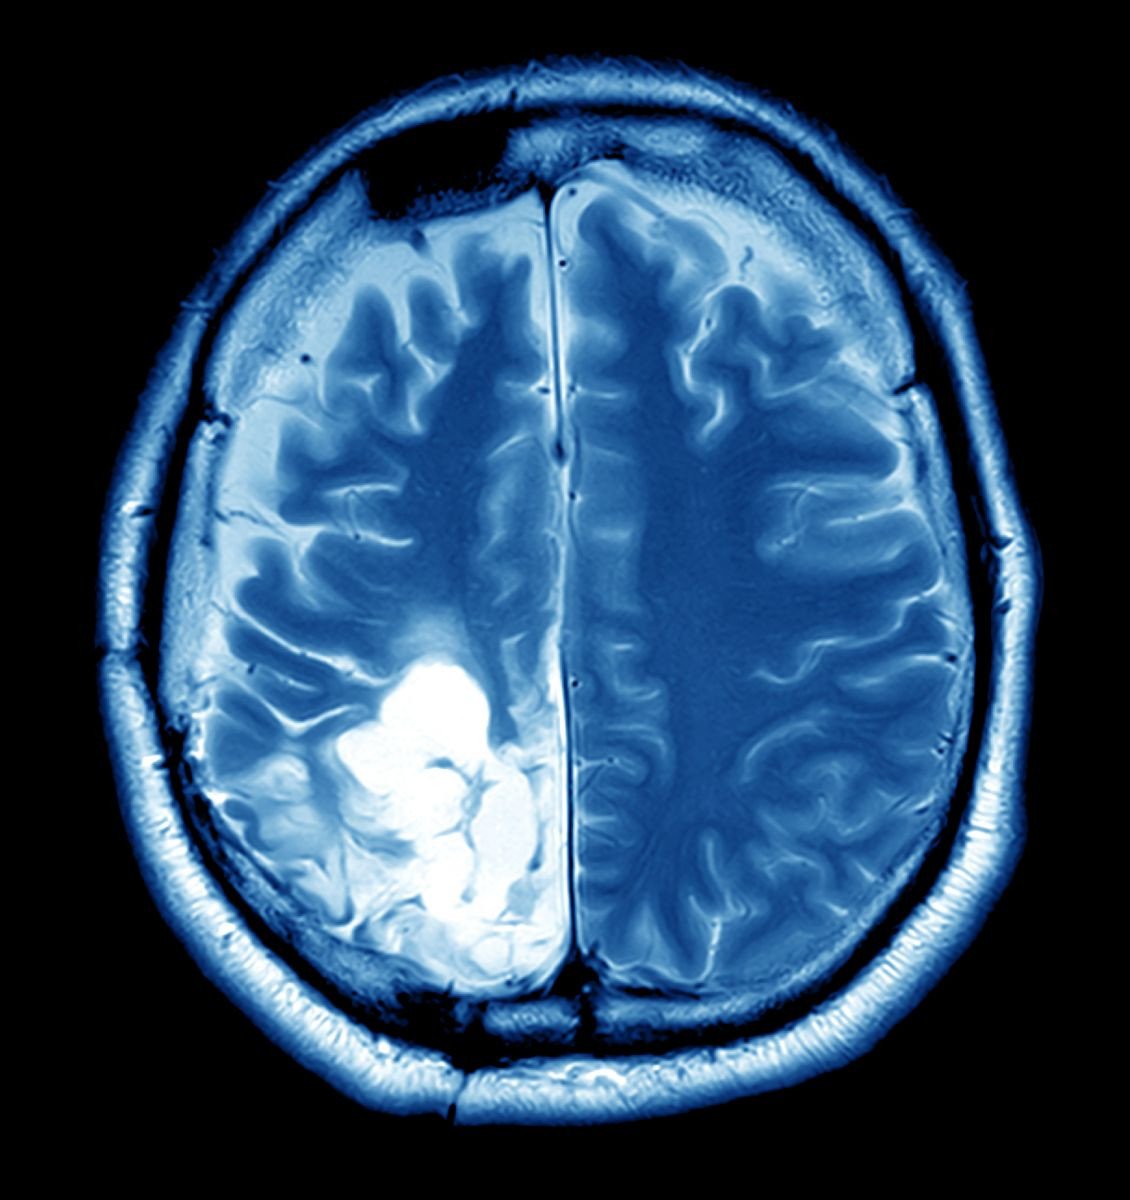

For months, Ravi experienced persistent headaches and occasional dizziness. Initially dismissing these symptoms as stress-related, he continued with his routine. However, the symptoms worsened, and his wife, Priya, insisted on a thorough medical examination. The diagnosis was a shock—a brain tumor. The news sent ripples of fear through the Sharma family, but it also ignited a determination in Ravi to fight back with all his strength.

The surgery was scheduled, and a team of experienced neurosurgeons meticulously planned every step. The procedure involved removing the tumor with precision, minimizing risks, and ensuring Ravi's brain functions remained intact. For the Sharma family, this was more than just a medical intervention—it was a pivotal moment filled with hope and anxiety.